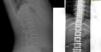

El caso 2 es una niña de 59/12 años, de origen búlgaro, padres sanos no consanguíneos, embarazo controlado normal, parto eutócico a término con un peso de 3.030g y una longitud de 50cm, periodo neonatal, desarrollo psicomotor y ponderoestatural adecuados. Intervenida a los 4 años por mielogénesis imperfecta y policaries, precisando de varios implantes dentales. Controlada en oftalmología por epífora. A los 5 años, durante un episodio febril se objetiva en radiografía de tórax un aumento de densidad ósea generalizada mayor en esternón y columna vertebral. A la exploración física y neurológica destaca malposición dentaria con múltiples caries, siendo el resto normal. En la radiografía de cráneo aparece aumento de densidad ósea en calota, huesos de la base y cuerpos vertebrales cervicales, compatible con osteopetrosis (fig. 2). Ante la sospecha de alteración en el metabolismo óseo, se realiza bioquímica completa con marcadores de recambio óseos destacando un aumento de fosfatasa alcalina ósea (92,1U/l) y propéptido C-terminal de colágeno tipo I (231,1ng/ml), resto normal. En la DMO se aprecia un Z-score de +7,4, siendo normal en ambos padres. Estudio otorrinolaringológico y oftalmológico normales. Actualmente está pendiente de estudio genético.

El caso 3 se trata de un paciente de 146/12 años, cuya madre y hermano presentan escoliosis leve. Embarazo y parto sin incidencias, con un peso de 3.570g y una longitud de 49cm, periodo neonatal sin alteraciones. Buen desarrollo ponderoestatural y psicomotor. En radiografía de columna (realizada para descartar escoliosis), presenta un aumento generalizado de la densidad mineral ósea en vértebras (fig. 3), costillas y huesos ilíacos. La exploración física normal, sin antecedentes de fracturas. Se realiza una DMO con Z-score +3,1. Entre los marcadores óseos realizados destaca fosfatasa alcalina ósea de 137,3U/l, osteocalcina de 113,2ng/ml, siendo el resto de analítica, orina y electroneurograma normales. Las densitometrías óseas por ultrasonidos realizadas a padres y hermano resultaron normales. Actualmente, el paciente está asintomático, con una DMO con Z-score de +2,7 y pendiente del estudio genético.